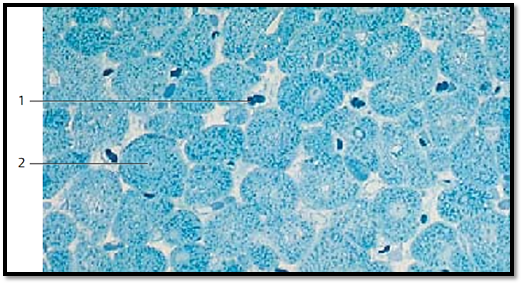

Cardiac Muscle—Myocardium—Left Ventricle

Cross-sections through cardiac muscle cells show the faintly stained central nuclei 2 and the Cohnheim fields or groups. The latter are base d on the formation of fibril bundles from myofibrils ( myofibril fields). The spaces between them contain sarcoplasm. Numerous capillaries 1 , which often still contain erythrocytes, are found in the loose connective tissue between muscle cells.

1 Capillaries

2 Nucleus of a cardiac muscle cell

Semi-thin section; stain: methylene blue-azure II; magnification: × 400